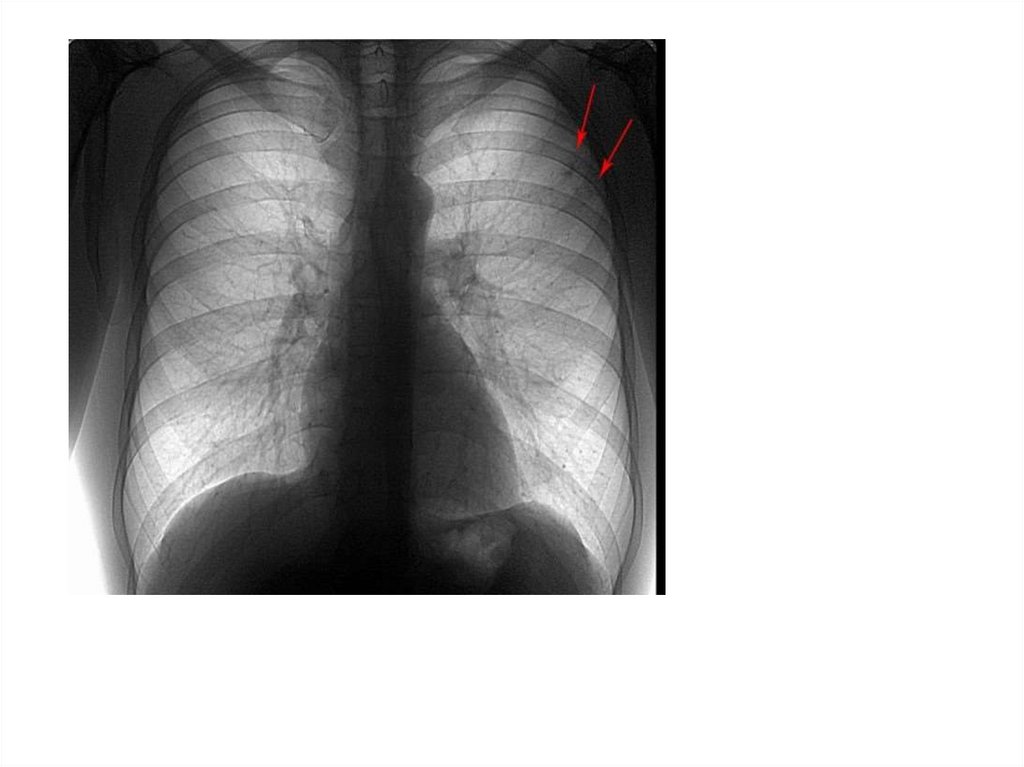

Рентгенограмма №1

30. Рентгенограмма №1